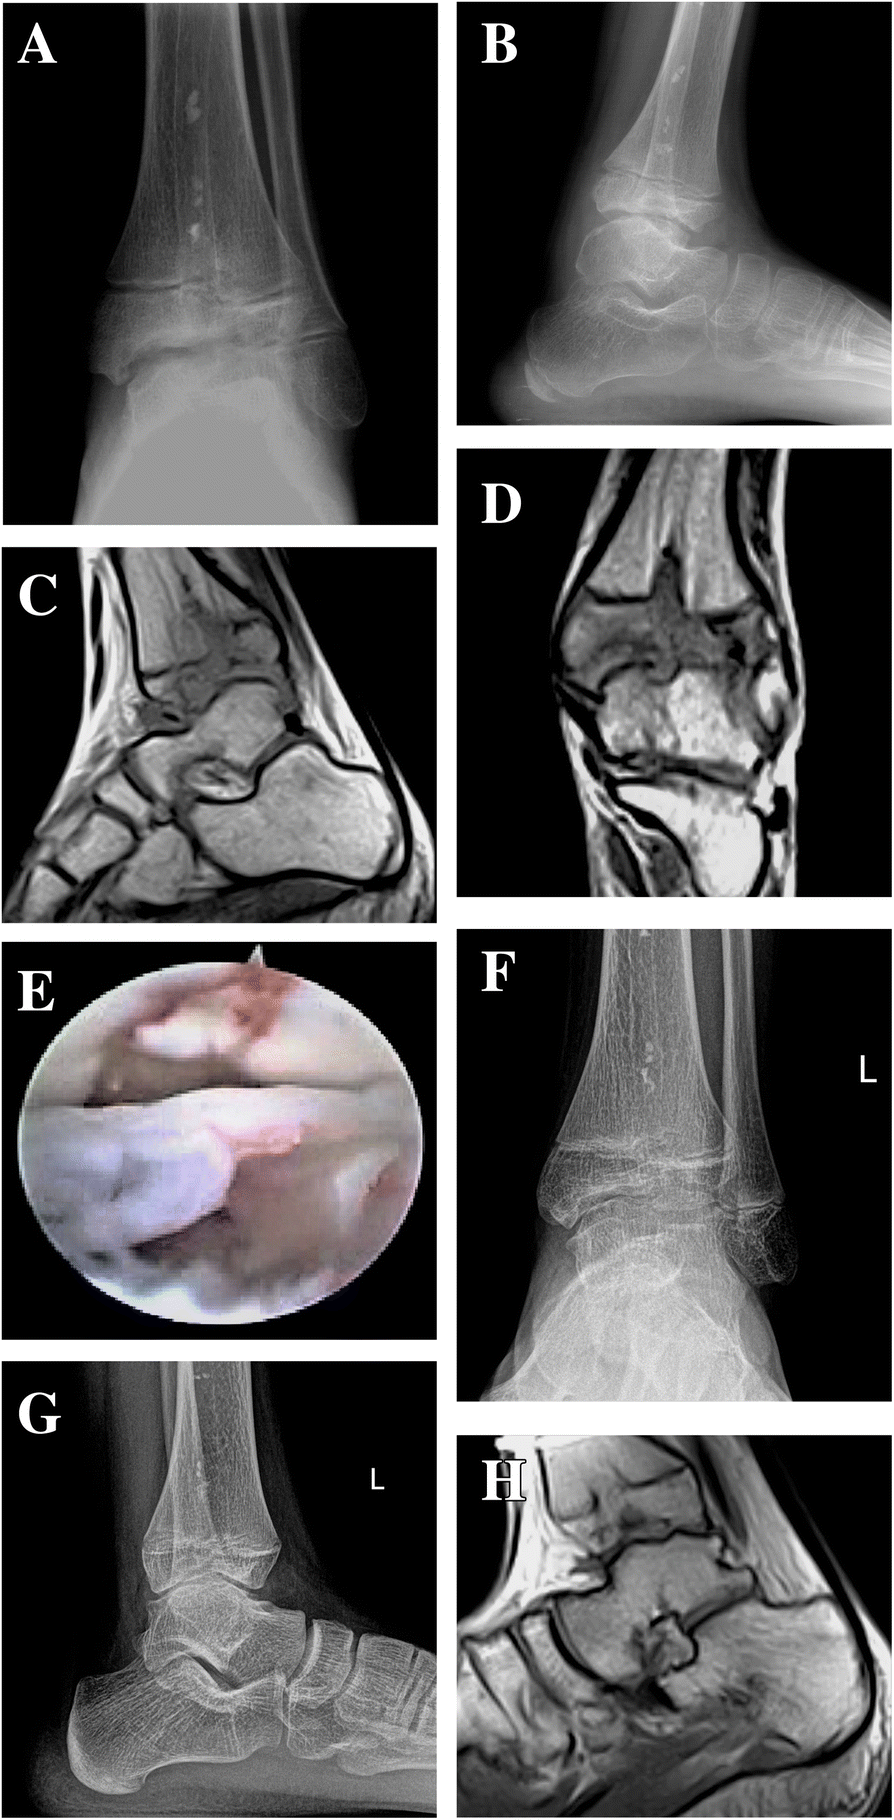

21+ Ankle Joint Mri Anatomy Radiology. When the capsule is thickened, it may cause impingement or synovitis, which can be in this patient there is only a small effusion in the ankle joint. On the non fatsat images there is subtle thickening of the capsule, with reactive changes.

Basic radiological anatomy of the brain and spine with annotated ct and mri images covering the brain, including the brainstem structures and ventricles, and whole spine. The imaging process allows the magnetic field to find changes in the organ and tissue structures. When the capsule is thickened, it may cause impingement scroll through the image stack for the ligamentous anatomy in the axial plane.

Sagittal cross section of the ankle and foot based on mri showing ankle joint, and tendos (calcaneal tendo, tibialis anterior, extensor hallucis. The ankle is the joint that is located between the leg and the foot. Balenciaga triple s black green. Suggested sequence, parameters and planning.